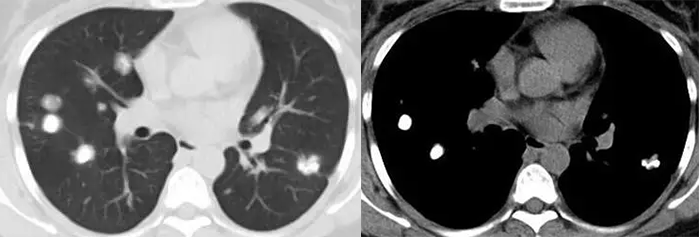

空洞性肺转移瘤

文献报道空洞型肺转移主要来自鳞癌和腺癌,鳞癌占 1/2 ~ 2/3,主要来自男性头颈部与女性生殖器肿瘤,其余为腺癌,主要来自结肠与乳腺癌。单亦有研究认为空洞性转移主要来自腺癌。其产生机制可能与鳞癌中心角化物排空、腺癌黏液样退变后黏液排空、肿瘤血供不足引起坏死、肿瘤继发脓肿、化疗、阻塞性肺气肿等有关。空洞性肺转移瘤变化快,短期内可见肿瘤增大、增多。CT 上空洞型转移结节外形上多保持了转移瘤的基本特点,即多发、圆形、边缘光整。洞壁多薄而均匀,内外壁光整,直径多 < 1.0 cm,部分洞壁厚薄不均,厚壁空洞病变可随着病灶增大而出现分叶、毛刺及壁结节等恶性空洞特点,部分空洞型肺转移洞壁可菲薄(称空泡更合适)。

54 岁男性,肾癌病史。左肺下叶厚壁空洞性转移(穿刺证实),左肺另见不伴空洞的实性小结节转移灶。